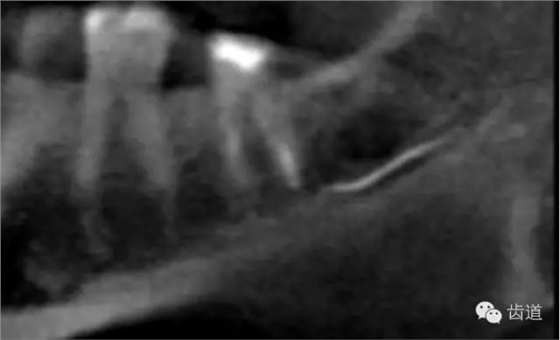

2.解剖因素:下頜牙齒根尖距下頜管太近,有些牙根與下頜管相連,以下頜第二恒磨牙多見

左下7根充后下唇麻木

左下5根管預(yù)備后下唇麻木

1.作根管治療前拍X線片,下頜牙齒應(yīng)特別注意與下頜管的關(guān)系。

2.準(zhǔn)確測(cè)量根管工作長(zhǎng)度,各種操作均在工作長(zhǎng)度范圍內(nèi)進(jìn)行。根管封藥不可過飽和,防止藥液溢出根尖孔。